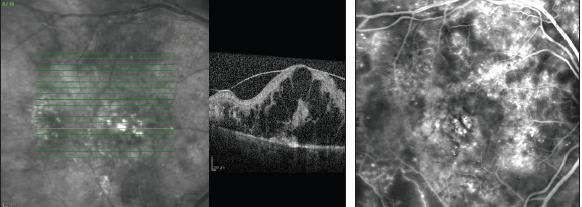

In DME, SD-OCT reveals various pathologic findings on qualitative and quantitative levels, as well as abnormal morphology of retinal layers.4 The qualitative interpretation includes hyper-reflective (hard exudates and cotton wool spots), hyporeflective (intraretinal edema, exudative retinal detachment, and cystoid macular edema), and shadow effect (hemorrhage, exudates, and retinal vessels). Examples can be seen in Figure 1.

Figure 1. The Spectralis HRA+OCT images in one patient (top) show cystoid swelling with intact outer retinal layer, external limiting membrane, photoreceptor inner segment, outer segments, and retinal pigment epithelium, as compared to another patient (bottom), who shows severe cystoid swelling and disturbed outer retinal layers.